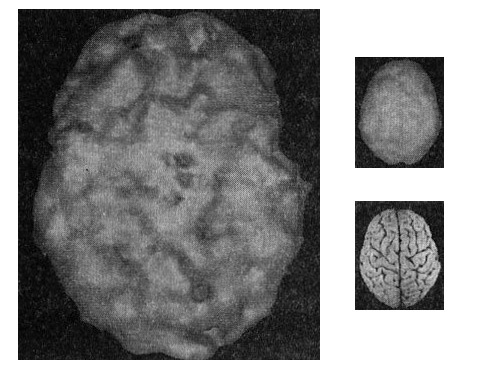

Люди, владеющие всей полнотой информации, знают, что наркотики повреждают мозг, но находятся и такие, кто в это не верит. Под наркотиками я имею в виду алкоголь, героин, метамфетамины, кокаин, вещества для вдыхания (худшие их всех), марихуану, ЛСД, экстази и другие. Я впервые заинтересовался томографией, когда работал главой отделения, в котором лечились пациенты с двойным диагнозом (психиатрическое расстройство плюс зависимость). В нем я видел больше тысячи сканов мозга наркоманов (рис. 10.4), и на подавляющем большинстве из них ущерб мозгу был заметен с первого взгляда.

Мозг наркомана

Рис. 10.4 Вид сверху

Мозг 22-летнего наркомана с пристрастием к алкоголю и кокаину: повсеместно нарушенная «рваная» картина работы мозга